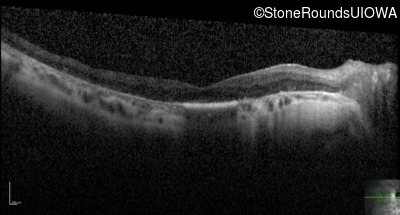

Optical Coherence Tomography - Right - 20/80

Exemplar / OCT Stack